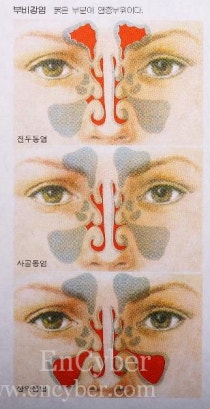

병에 걸리면 증상에 따라 고통을 받습니다.그중에서도 특히 코는 생활 속에서 밀접한 관련이 있기 때문에 고통의 강도가 크다고 할 수 있습니다.코 질환의 종류로는 여러 가지가 있는데 그 중에서 얼굴 무게가 느껴지면 인천 서구 축농증을 의심해 보겠습니다.

이 병의 증상은 노란색이나 녹색 콧물 혹은 얼굴 무게, 가려움증, 재채기 등이 느껴집니다.무엇보다 코막힘으로 일상생활을 도저히 영위할 수 없을 정도이기 때문에 가급적 증상이 처음 느껴졌을 때 치료에 들어가는 것이 좋습니다.

치료는 환자가 현재 어떤 상황에 처해 있는지에 따라 달라집니다.이때 상황은 어떤 것일까요? 우선 부비강과 코가 연결된 통로를 폐쇄할지가 중요합니다.이부분이막혔는지열려있는지에따라달라져요.